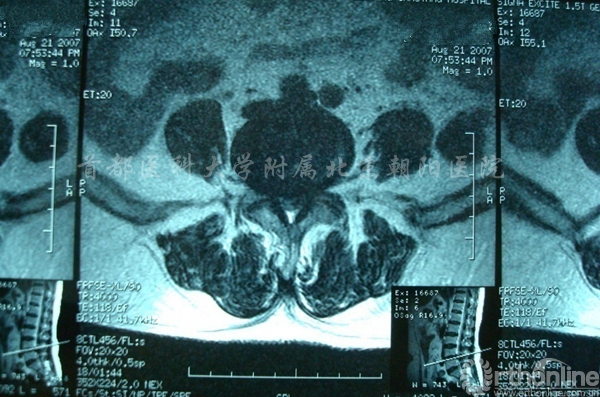

腰椎间盘突出合并椎管狭窄术前MRI